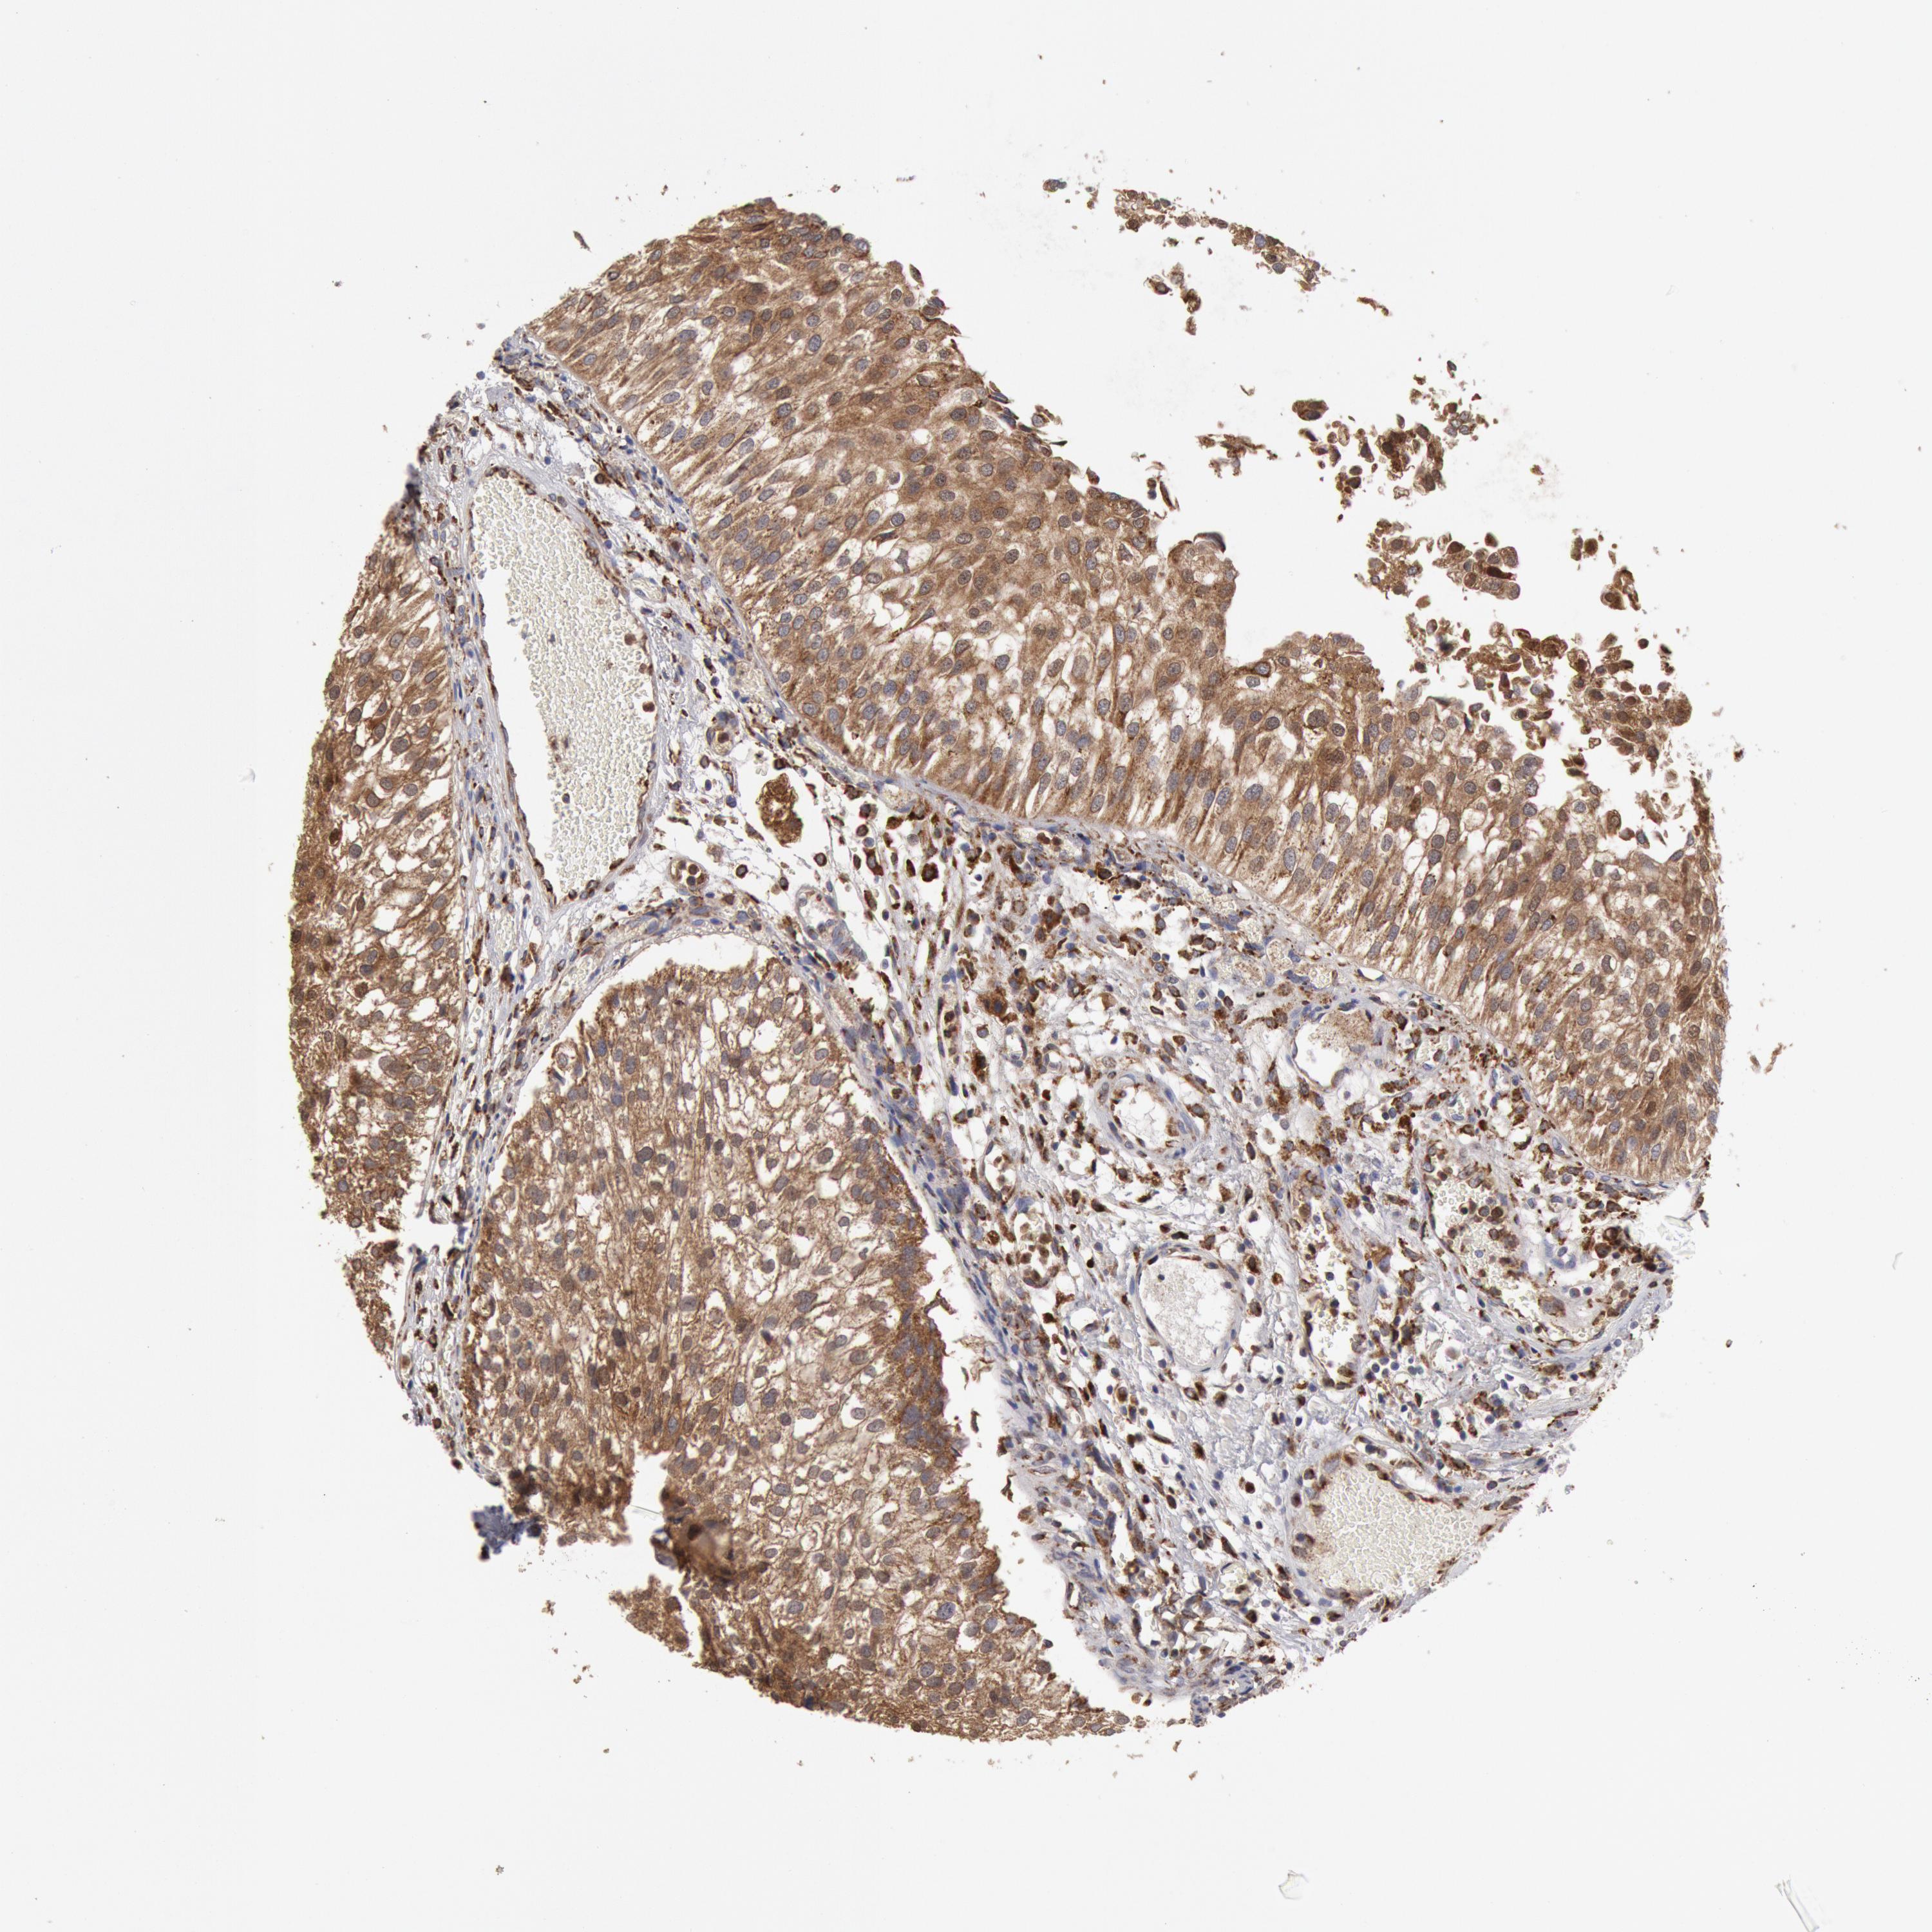

UROTHELIAL CANCER - Protein expressioni

A mouse-over function shows sample information and annotation data. Click on an image to view it in a full screen mode. Samples can be filtered based on level of antibody staining by selecting one or several of the following categories: high, medium, low and not detected. The assay and annotation is described here.

Note that samples used for immunohistochemistry by the Human Protein Atlas do not correspond to samples in the TCGA dataset.

Antibody stainingi

Antibody staining in the annotated cell types in the current human tissue is reported as not detected, low, medium, or high, based on conventional immunohistochemistry profiling in selected tissues. This score is based on the combination of the staining intensity and fraction of stained cells.

Each image is clickable and will lead to virtual microscopy that enables deeper exploration of all samples and also displays staining intensity scores, fraction scores and subcellular localization as well as patient and tissue information for each sample.

Antibody HPA001318

Staining

High

Medium

Low

Not detected

Intensity

Strong

Moderate

Weak

Negative

Quantity

>75%

75%-25%

<25%

None

Location

Nuclear

Cytoplasmic/membranous

Cytoplasmic/membranous,nuclear

Urothelial carcinoma, High grade